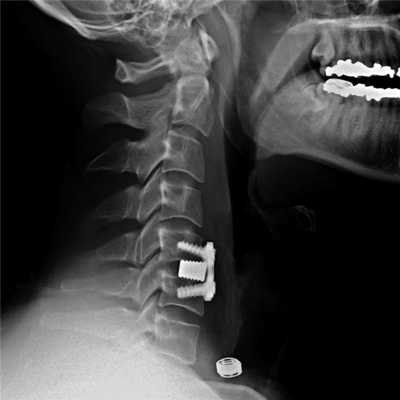

Для замещения удаленных позвонков у 8 (28%) больных применен сетчатый титановый протез «MASH» (рис. 1), который использовался нами с 2006 по 2010 г. Телескопическая система эндопротезирования, которая использовалась с 2010 по 2016 г., применена у 21 (72%) пациента (рис. 2). Спондилодез при помощи пластин выполнен у 19 (65,5%) больных, комбинированная стабилизация (титановые винты и пластины) — у 10 (34,5%) пациентов.

Рис. 1. Вертебрэктомия позвонка LIV с замещением дефекта сетчатым эндопротезом тела позвонка системой «MASH» и транспедикулярной фиксацией. а — интраоперационная фотография; б — послеоперационная рентгенограмма поясничного отдела позвоночника.